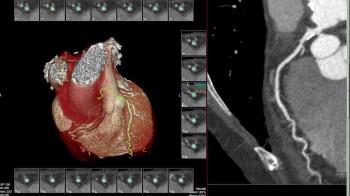

• MSCT koronarografija (prikaz krvnih žila srca CT-om, bez neugodnosti i komplikacija koje nosi klasična koronarografija), u saradnji s Poliklinkom dr.Al-Tawil